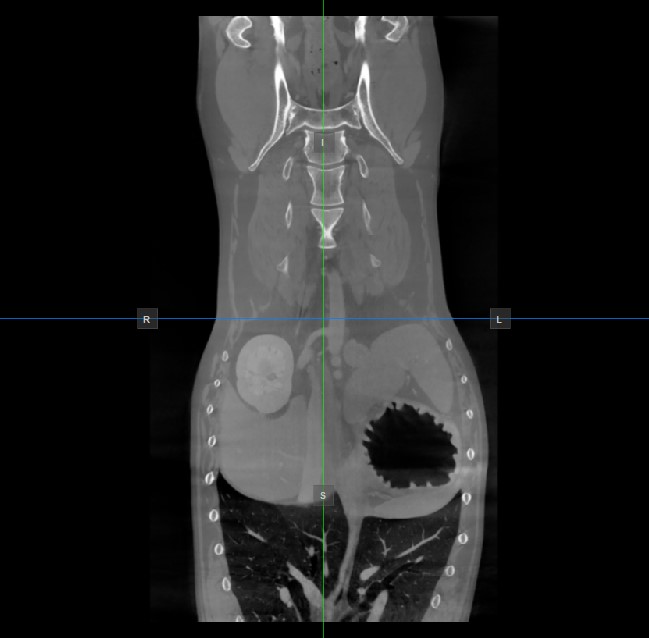

Die Position und der Schnitt der beiden anderen Bildebenen, die im aktiven Viewport nicht dargestellt werden, wird durch zwei vertikale und horizontale Linien angezeigt, die als Slicer bezeichnet werden. Die Endpunkte jedes Slicers sind mit einem Buchstaben gekennzeichnet, der der entsprechenden Richtung/Seite des 3D-Volumens entspricht, basierend auf dem RAS-Koordinatensystem.

Auf jedem 2D-Viewport werden nur vier der verfügbaren sechs Seiten angezeigt. Die Beschriftungen und die entsprechenden Seiten sind wie folgt:

Patient rechts (R), zeigt die rechte Körperseite an

Patient links (L), zeigt die linke Körperseite an

Anterior (A), zeigt die Vorderseite des Körpers an

Posterior (P), zeigt die Rückseite des Körpers an

Superior (S), zeigt die Oberseite des Körpers an

Inferior (I), zeigt die Unterseite des Körpers an